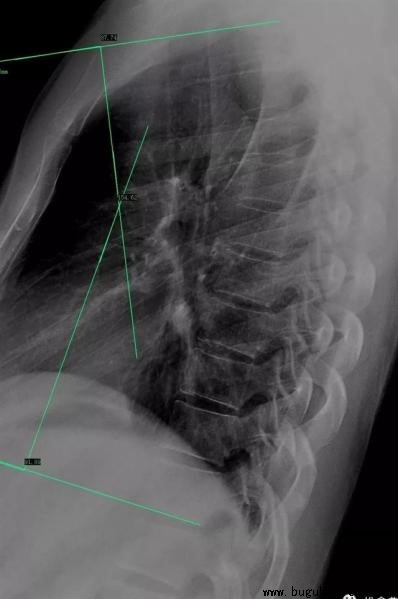

胸椎:正常的胸椎曲度主要由T1~T12胸椎形成,并以T6~T7椎体作为顶点,另外通过T2椎体上缘和T11椎体下缘分别做一切线,形成一夹角,正常范围是20°~50°。胸曲大于50°也就是胸曲过大,也就是临床见到的“驼背”情况。这其中主要出现2种类型的曲度改变,一种为胸段后凸,另一种则为胸腰段后凸。胸段后凸较为常见,常涉及T2~T12节段,顶椎常位于T6~T8节段。胸腰段后凸相对较少,常涉及T5~L4节段,顶椎常位于胸腰交界区附近。